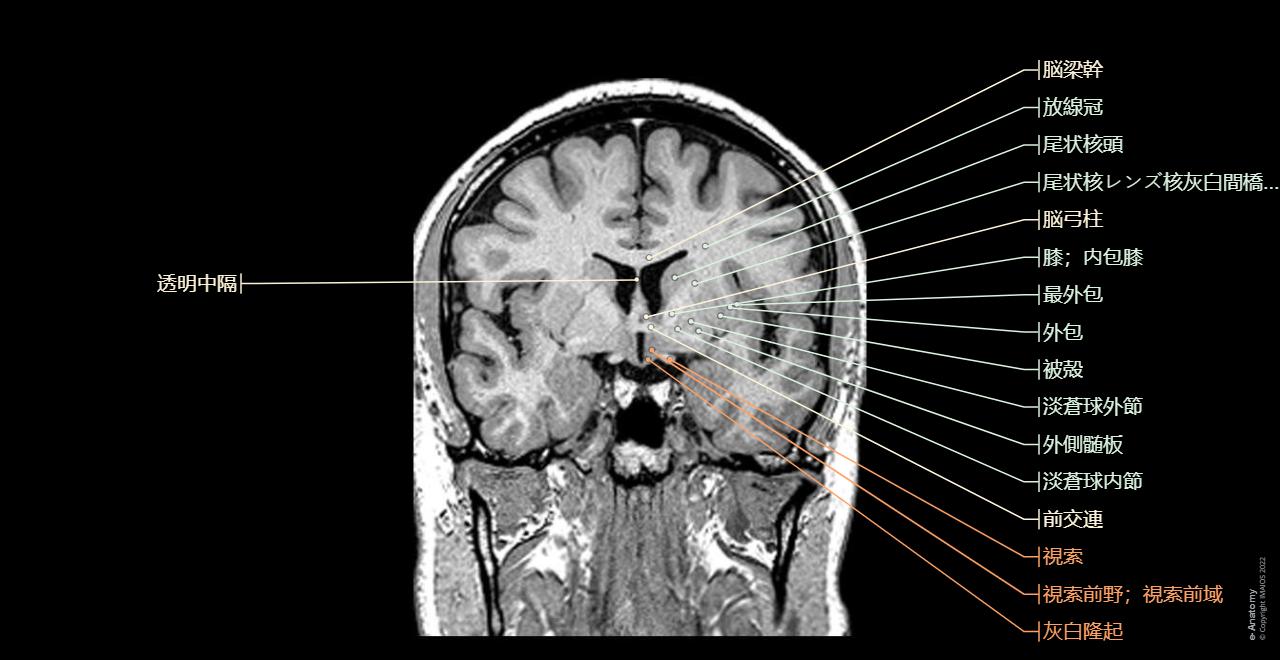

大脳 冠状断面<< 神経系 << バイオメディカル CG ライブラリー << 株式会社メタ・コーポレーション・ジャパン。

脳 MRI 3D : 正常解剖学e-Anatomy。

经下丘冠状面层面 枕颞沟呈“11”型,白色实线为枕颞沟,红色实线为侧副沟。